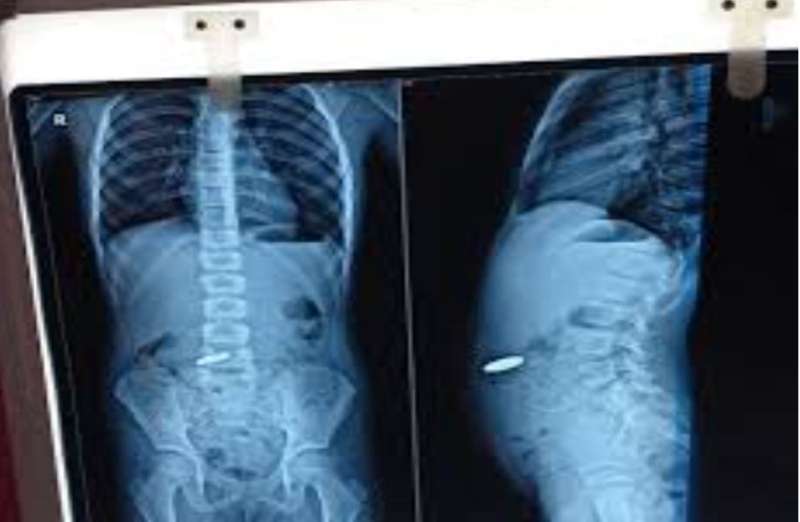

बच्चे को बुधवार देर रात 11 बजे इमरजेंसी में उपचार के लिए लाया गया। बच्चे की एक्सरे जांच में तीन सिक्के खाने की नली में फंसे दिखे। उपचार के लिए तुरंत बच्चे को ऑपरेशन थियेटर लेकर गए। डॉक्टरों की टीम ने एनेस्थीसिया देकर एसोफैगोस्कोपी प्रक्रिया के जरिए सिक्के बाहर निकाले। इसमें दो पांच रुपये के सिक्के और एक दस रुपये का सिक्का शामिल था।